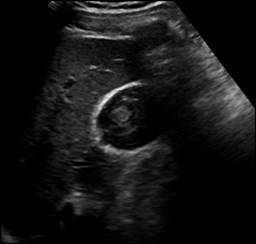

Se decide continuar vigilancia y realizar USG de control a las 27 horas de evolución, en el cual se reportó laceración hepática grado I de la AAST (American Association for the Surgery of Trauma) de 60 mm en su eje longitudinal, y vesícula biliar como se describe en la Figura 2.

Figura 2: Ultrasonido con líquido laminar subhepática, vesícula biliar de paredes delgadas, contenido de características hemorrágicas.